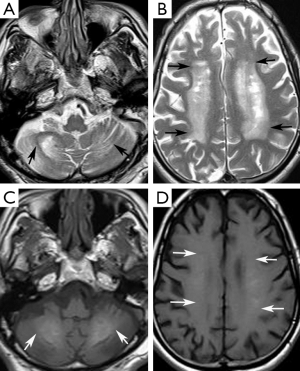

A 74-year-old man presented at our neurology outpatient clinic with headache, progressive short-term memory deficit for 1 year, and weakness of the upper and lower extremities with tremor. Neurological examination with standard neuropsychological tests showed slight cognitive deficit, characterized by memory impairment. Cranial MRI revealed diffuse symmetrical hyperintense signal in the bilateral basal ganglia, dentate nuclei, and also involving the periventricular white matter and centrum semiovale bilaterally on T2-weighted and FLAIR images (Figure 1A,B). T1-weighted images showed mild hyperintense signal changes in the dentate nuclei and minimal hyperintensity in the centrum semiovale (Figure 1C,D). In addition, cerebral and cerebellar atrophy was noted (Figure 1). These signal changes were hypointense on SWI minimal intensity projection (minIP) and phase images, consistent with calcification (Figure 2A-D). Brain CT imaging confirmed calcifications. (Figure 2E,F). Electroencephalogram (EEG) was normal. Laboratory data including metabolic tests which were performed to investigate calcium deposition disorders (including Ca/P, parathormone hormone) were unremarkable. On the basis of laboratory test results, neuroimaging findings, and clinical data, FD was diagnosed.